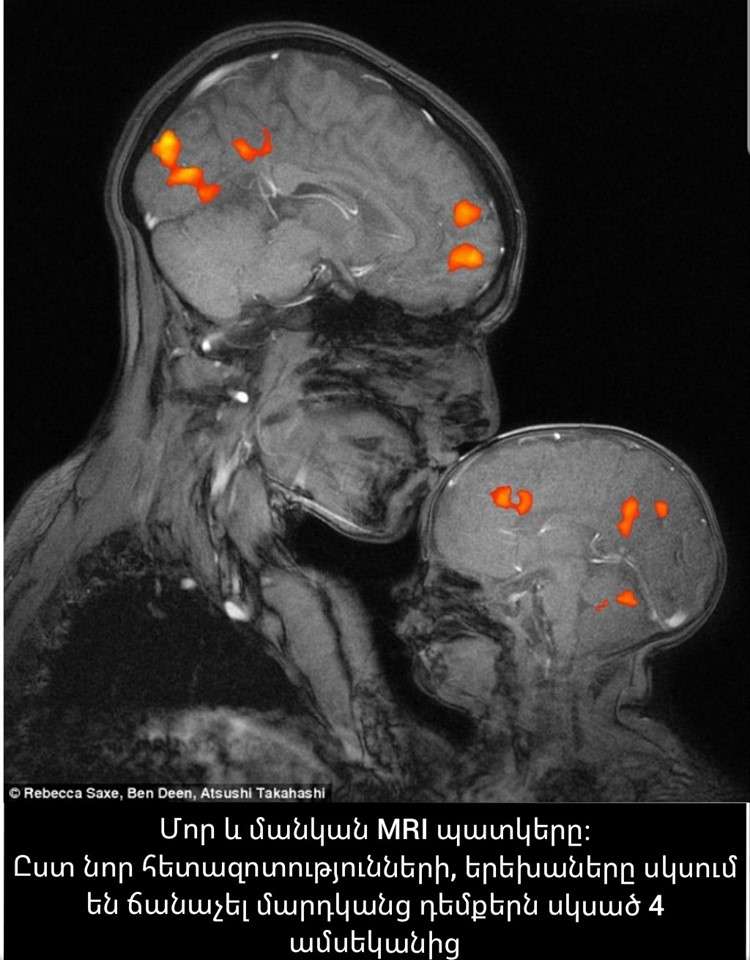

Վերջերս կենսաբանները մի ցնցող հայտնագործություն են արել։ Պարզվել է, որ օրգանիզմում առկա մի հորմոնի՝ օքսիտոցինի (Oxytocin) քանակությունը երեխայի մոտ ավելանում է, երբ նա հպվում է բիոլոգիական մորը։ Որդեգրված երեխաների մոտ այս հորմոնի քանակությունը հաստատուն է մնում։

Վերջերս պարզվել է, որ, բացի մինչ այժմ հայտնի մի շարք կարևոր գործառույթներից, օքսիտոցին հորմոնը պատասխանատու է երեխայի՝ սոցիալական խմբում ինքնաարտահայտման համար։ Օքսիտոցինի բավարար քանակության դեպքում երեխան կարող է ագրեսիվ պաշտպանել ինքն իրեն՝ պատասխանել իրեն ծաղրողներին։ Եվ պատահական չէ, որ ծնող(ներ) չունեցող երեխաները հաճախ հայտնվում են սոցիումի հետնաբակում՝ ամենևին արժանի չլինելով դրան։ Այս դեպքում, ի հավելումն խախտված սոցիալական նորմերի, երեխայի մոտ բացակայում է անհրաժեշտ քանակի օքսիտոցինը, որը շատ բացասական է արտահայտվում նրա սոցիալական վարքագծի վրա։

Ծնողները, հաճախ գրկելով ու սիրելով երեխաներին (բնական պահանջ է, անկախ իրենցից՝ անում են բոլոր ծնողները), օգնում են երեխաների մոտ գեներացնել բավարար քանակությամբ օքսիտոցին, և երեխան կարող է կայուն կանգնել կյանքի ողջ ընթացքում, իսկ լքելով երեխաներին, դարձնում են նրան ֆիզիոլոգիապես ոչ ամբողջական, իսկ հասարակության մեջ՝ ոչ ամբողջական անդամ։ Գուցե այստեղից էլ առաջացել է ժողովրդական իմաստուն խոսքը՝ «Արյունը ջուր չի դառնա»՝ նկատի ունենալով հարազատների կապվածությունը։